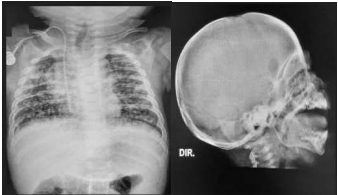

Lactente masculino, 6 meses de idade, é levado à emergência pediátrica por sua mãe devido ao surgimento de “caroços” em pescoço e na virilha há cerca de 1 mês. Nos últimos dias, refere que o menor está mais irritado, além de perceber a respiração mais “rápida”. Relata que a criança apresentou picos febris em alguns dias ao longo desse período

O exame físico chamou a atenção do pediatra nos seguintes aspectos:

- Leve palidez; irritabilidade durante todo o exame físico; linfonodos palpáveis em regiões cervical e inguinais bilaterais, com os maiores medindo cerca de 3 cm; frequência respiratória de 60 incursões por minuto; fígado palpável a 4 cm do rebordo costal direito.

Solicitados exames:

- Hemograma: HGB 10,5 g/dL VCM 70 fL HCM 24 pg

- Leucócitos 12.450 mm3 / Plaquetas 165.000 / mm3

- RX tórax (vide imagem abaixo). *O laudo do radiologista evidenciou, entre outros achados, lesões osteolíticas em ambas as escápulas. Foi sugerido realizar RX de crânio (vide abaixo).